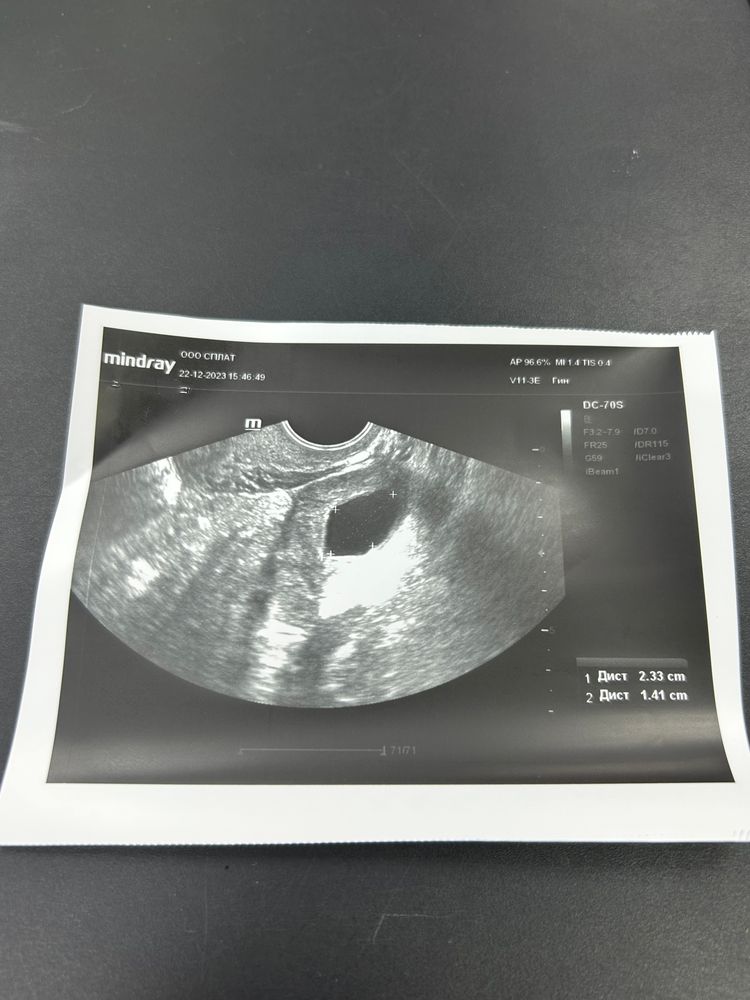

Кто понимает, напишите есть шанс в этом цикле?

Так у вас не было овуляции. У вас она ушла в кисту. Рассосётся в течение цикла. У вас даже написано кистозное образование в правом яичнике

Анастасия , у девушки не фолликулярная киста ( когда фолликул не лопнул), а киста желтого тела, уже когда фолликул совулировал.

Анастасия , была. Там и киста и желтое тело

Что то вам не то пишут…..Судя по заключению овуляция вот только недавно была, так как есть жидкость в полости малого таза! А киста - это киста желтого тела, она образовалась уже после овуляции, такое бывает. Если вы как раз старались пару дней назад, то шанс есть! И с кистой желтого тела беременность наступает. 😉🌺 Дальше дело случая.

На самом деле непонятно. У вас есть и жёлтое тело и киста в одном яичнике. Киста может быть ещё с прошлого цикла, тогда вообще неважно. Главное в этом цикле точно была овуляция, беременность скорее всего возможна. А киста сама уйдет.